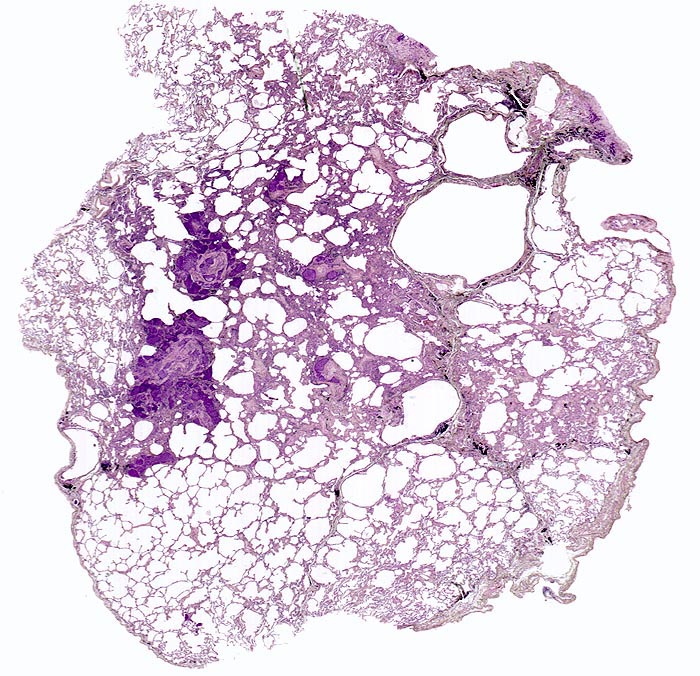

PathoPic – image database / PathoPic ID 4729 - Lymphangiosis carcinomatosa, zentroazinäres Lungenemphysem

Lymphangiosis carcinomatosa, zentroazinäres Lungenemphysem

In der Übersicht sind mehrere Tumorherde erkennbar sowie eine Destruktion des Lungenparenchyms im Bereich der mit Anthrakosepigment schwarz angefärbten Azinuszentren (zentroazinäres Emphysem).

Metastasierendes Tumorleiden bei unbekanntem Primärtumor. Autoptisch primäres peripheres neuroendokrines Karzinom der Lunge mit ausgedehnter lymphogener und hämatogener Metastasierung.